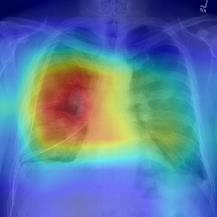

Thoracic disease detection from chest radiographs using deep learning methods has been an active area of research in the last decade. Most previous methods attempt to focus on the diseased organs of the image by identifying spatial regions responsible for significant contributions to the model's prediction. In contrast, expert radiologists first locate the prominent anatomical structures before determining if those regions are anomalous. Therefore, integrating anatomical knowledge within deep learning models could bring substantial improvement in automatic disease classification. This work proposes an anatomy-aware attention-based architecture named Anatomy X-Net, that prioritizes the spatial features guided by the pre-identified anatomy regions. We leverage a semi-supervised learning method using the JSRT dataset containing organ-level annotation to obtain the anatomical segmentation masks (for lungs and heart) for the NIH and CheXpert datasets. The proposed Anatomy X-Net uses the pre-trained DenseNet-121 as the backbone network with two corresponding structured modules, the Anatomy Aware Attention (AAA) and Probabilistic Weighted Average Pooling (PWAP), in a cohesive framework for anatomical attention learning. Our proposed method sets new state-of-the-art performance on the official NIH test set with an AUC score of 0.8439, proving the efficacy of utilizing the anatomy segmentation knowledge to improve the thoracic disease classification. Furthermore, the Anatomy X-Net yields an averaged AUC of 0.9020 on the Stanford CheXpert dataset, improving on existing methods that demonstrate the generalizability of the proposed framework.